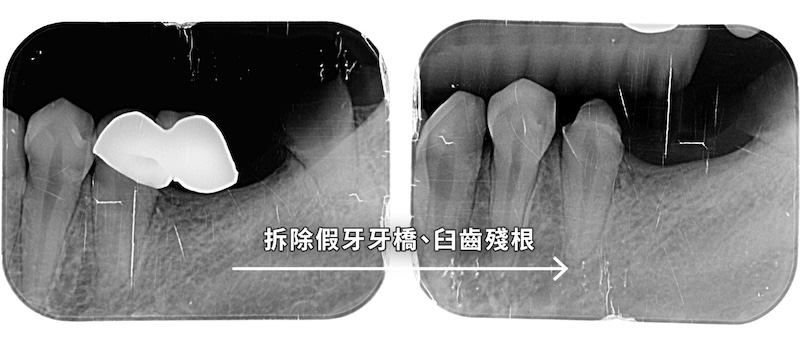

拔除殘根後,採用舒眠植牙手術置入兩支人工牙根。隨後執行「游離牙齦移植術」增加牙肉寬度與厚度,預防植體周圍發炎。

利用口內掃描與數位技術完成最終假牙,縮短療程並提升精準度。治療效果

成功重建咀嚼功能,增厚後的牙肉對植體形成良好保護,患者對於細心的療程解說與專業技術表示高度滿意。